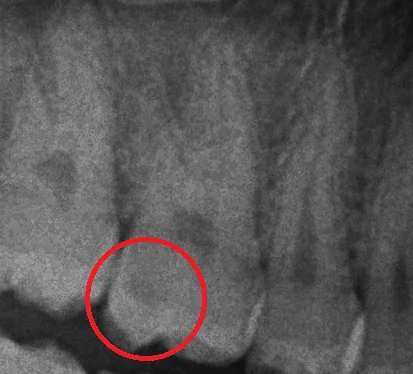

レントゲン像としてはこんな感じです。

うん。確かに虫歯が残っている。

私の知っているシールドレストレーションとはほとんどの虫歯を取り除くんですが・・・

思った以上にダイナミックに残っていますね。